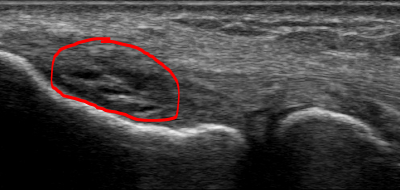

Orthobiologics and Epicondylosis: Tendon Healing Using Microfragmented Adipose Tissue and PRP

TERRANCE MANNING II, ND, RMSK A 53-year-old male presented to the clinic with persistent right lateral elbow pain. The pain onset was insidious, yet this patient had had recurrent symptoms for several years; the most recent episode started 8 months before this...